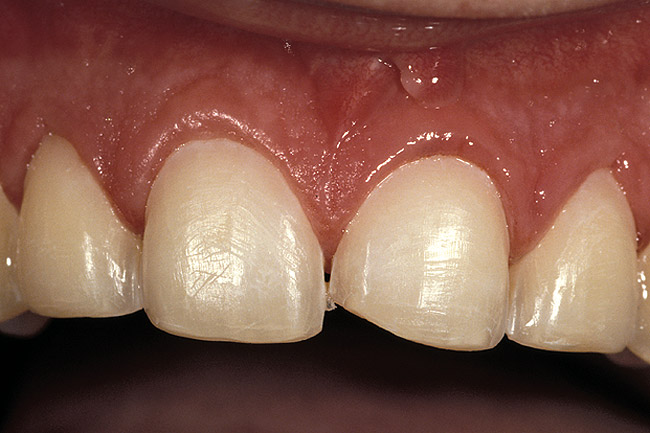

Figure 11  This is a 4-year recall photograph following placement of the final restorations.

Figure 11

Rule 3: If a sulcus greater than 2 mm is found on the facial, evaluate the teeth esthetically to see if a gingivectomy could be performed to lengthen the teeth and create a 1.5-mm sulcus. Then, treat using Rule 1 (Figure 6, Figure 7, Figure 8, Figure 9, Figure 10 and Figure 11).

The rationale for Rule 3 is that it is more difficult to place a margin one-half the depth of a deep sulcus as compared to 0.5 mm to 0.7 mm below tissue. In addition, the stability of the free gingival margin is less predictable with a deep sulcus than with a shallow sulcus. Therefore, if it is possible to perform a gingivectomy, lengthening the tooth and leaving a

1-mm to 1.5-mm sulcus, doing so will create a more predictable situation in which to place an intracrevicular margin. This does not, however, ensure that the tissue will remain at the level placed, because gingivectomies are frequently followed by some gingival rebound.